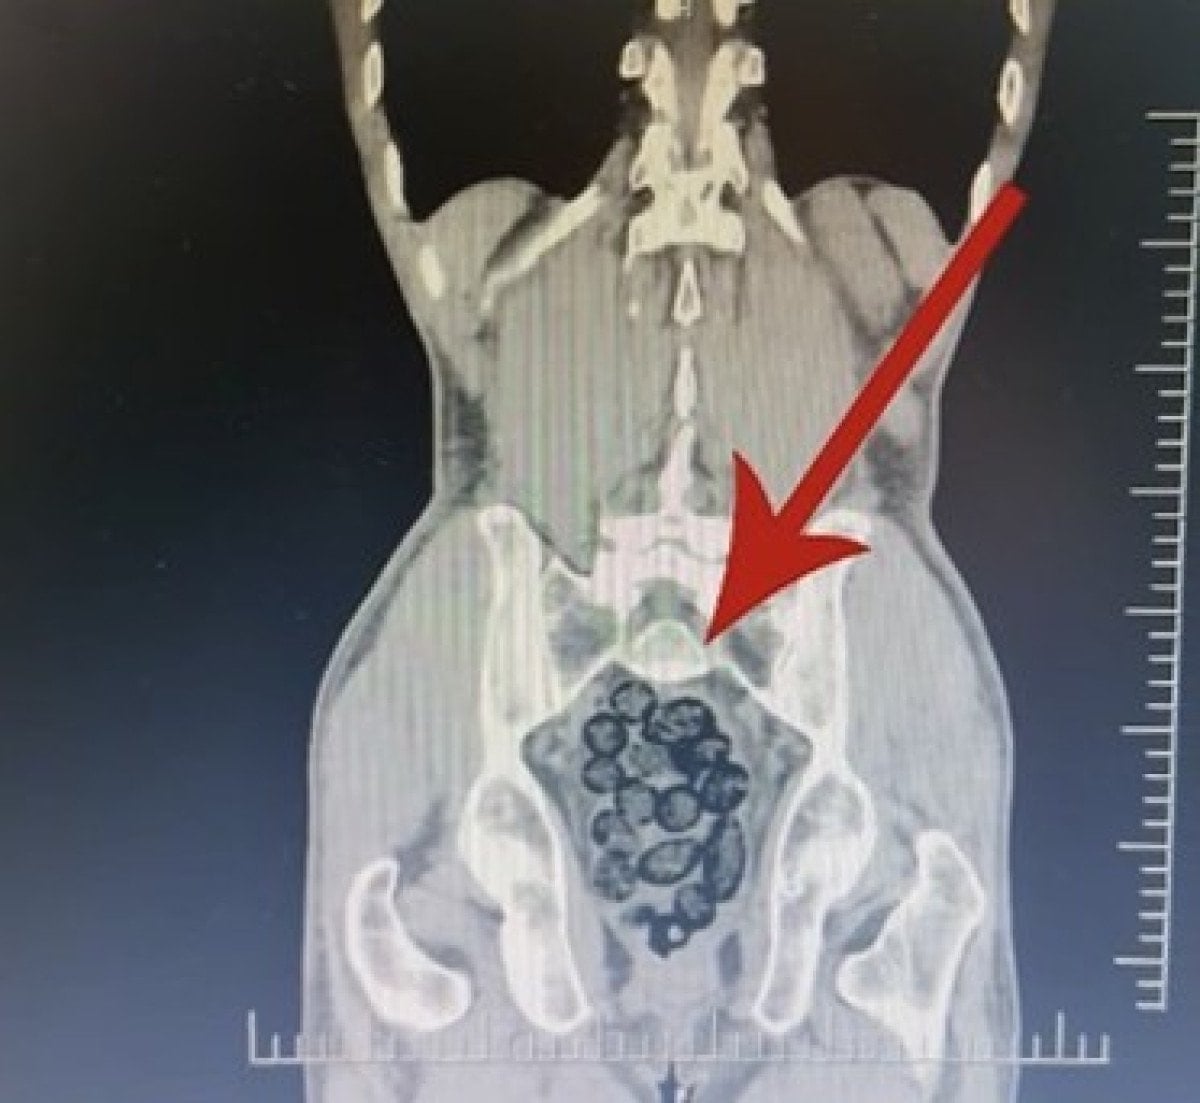

Yapılan incelemeler sonucunda yabancı uyruklu şahsın midesinde 64 parça halinde toplam 472 gram uyuşturucu maddesi metamfetamin olduğu belirlendi.

Gözaltına alınan şahsın midesindeki uyuşturucu madde çıkartıldı.